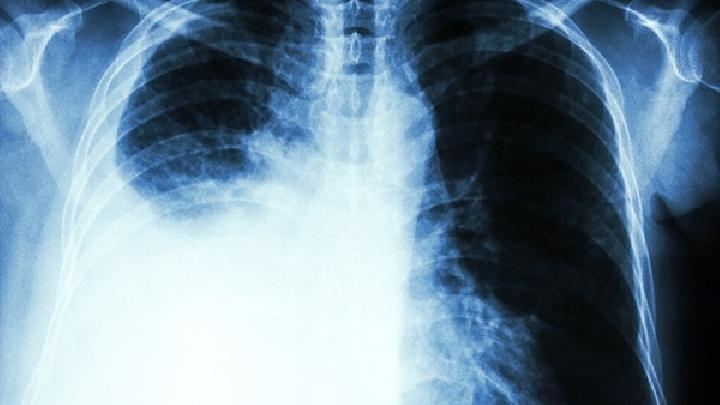

气胸